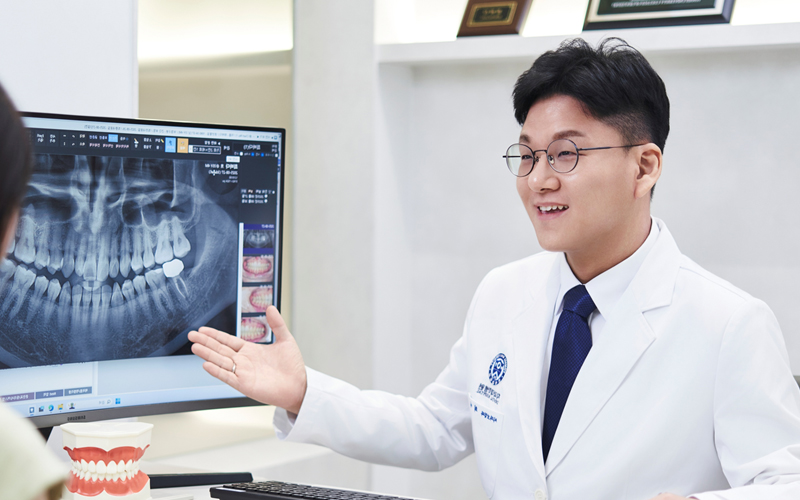

편안한 치과 치료를 위한

통증 최소화 진료 프로토콜

병점연세세브란스치과에서는 환자분들과 적극적인 소통으로 심리적 불안감을 덜어드리고

가글마취, 도포마취, 디지털 무통마취 등 세분화된 통증 최소화 진료 프로토콜을 적용해

치과 치료 과정에서의 공포감과 통증을 줄여 보다 편안한 치료가 가능합니다.